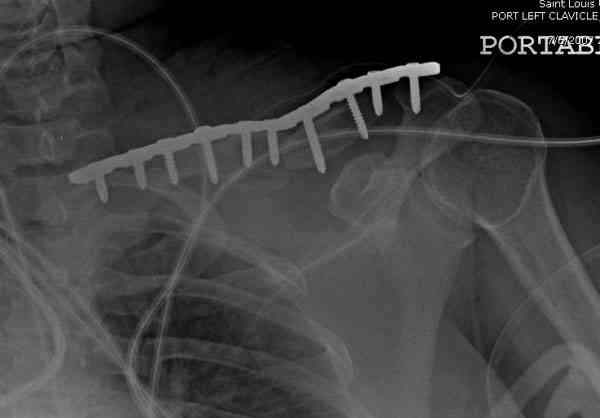

Недавно разбирали случай ложного сустава.

45 летная женщина после автоаварии, алкоголь 163 и 20 летним стажем курения.

Консервативное лечение, через 8 мес. операция Rockwood pin с костной пластикой в нашем городе другим врачом. После 8 недели падение, гвоздь удален оперирующим хирургом, больная направлена к нам. Фиксация реконструктивной пластиной с трикортикальным графтом, добавлен BMP-2. Для стабилизации фиксацию провели через акромион.

Вот уже два месяца больная также продолжает жаловаться на боли, буквально на днях удалили акромиальную часть пластины с специальной пилой с алмазным покрытием для медицинского металла. До сих пор судьба ложного сустава неизвестна....